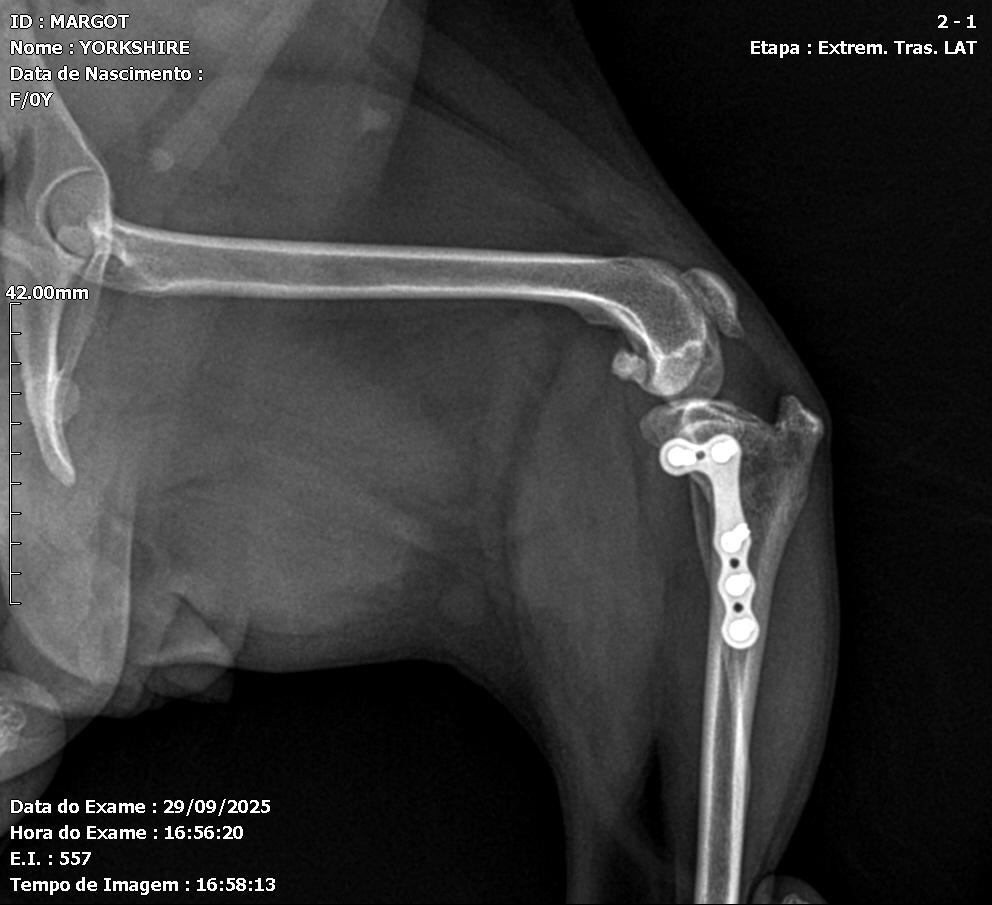

Postoperative evaluation included assessment of range of motion, limb alignment, and joint stability. Radiographs confirmed appropriate implant positioning and patellar alignment (Figures 4 and 5). A slight reduction of the medial femorotibial joint space was noted, with preservation of overall congruence. Mild lateral displacement of the patella was observed on the craniocaudal view and minimal caudal displacement on the mediolateral view. Increased soft-tissue opacity and volume, compatible with postoperative inflammatory changes, were also identified. The semicircular osteotomy in the proximal third of the left tibia and adequate implant positioning confirmed correct surgical execution.

Figures 4 and 5: Ventrodorsal and mediolateral radiographs of the left pelvic limb in the immediate postoperative period, showing fracture stabilization using an orthopedic plate and screws, with proper bone alignment.